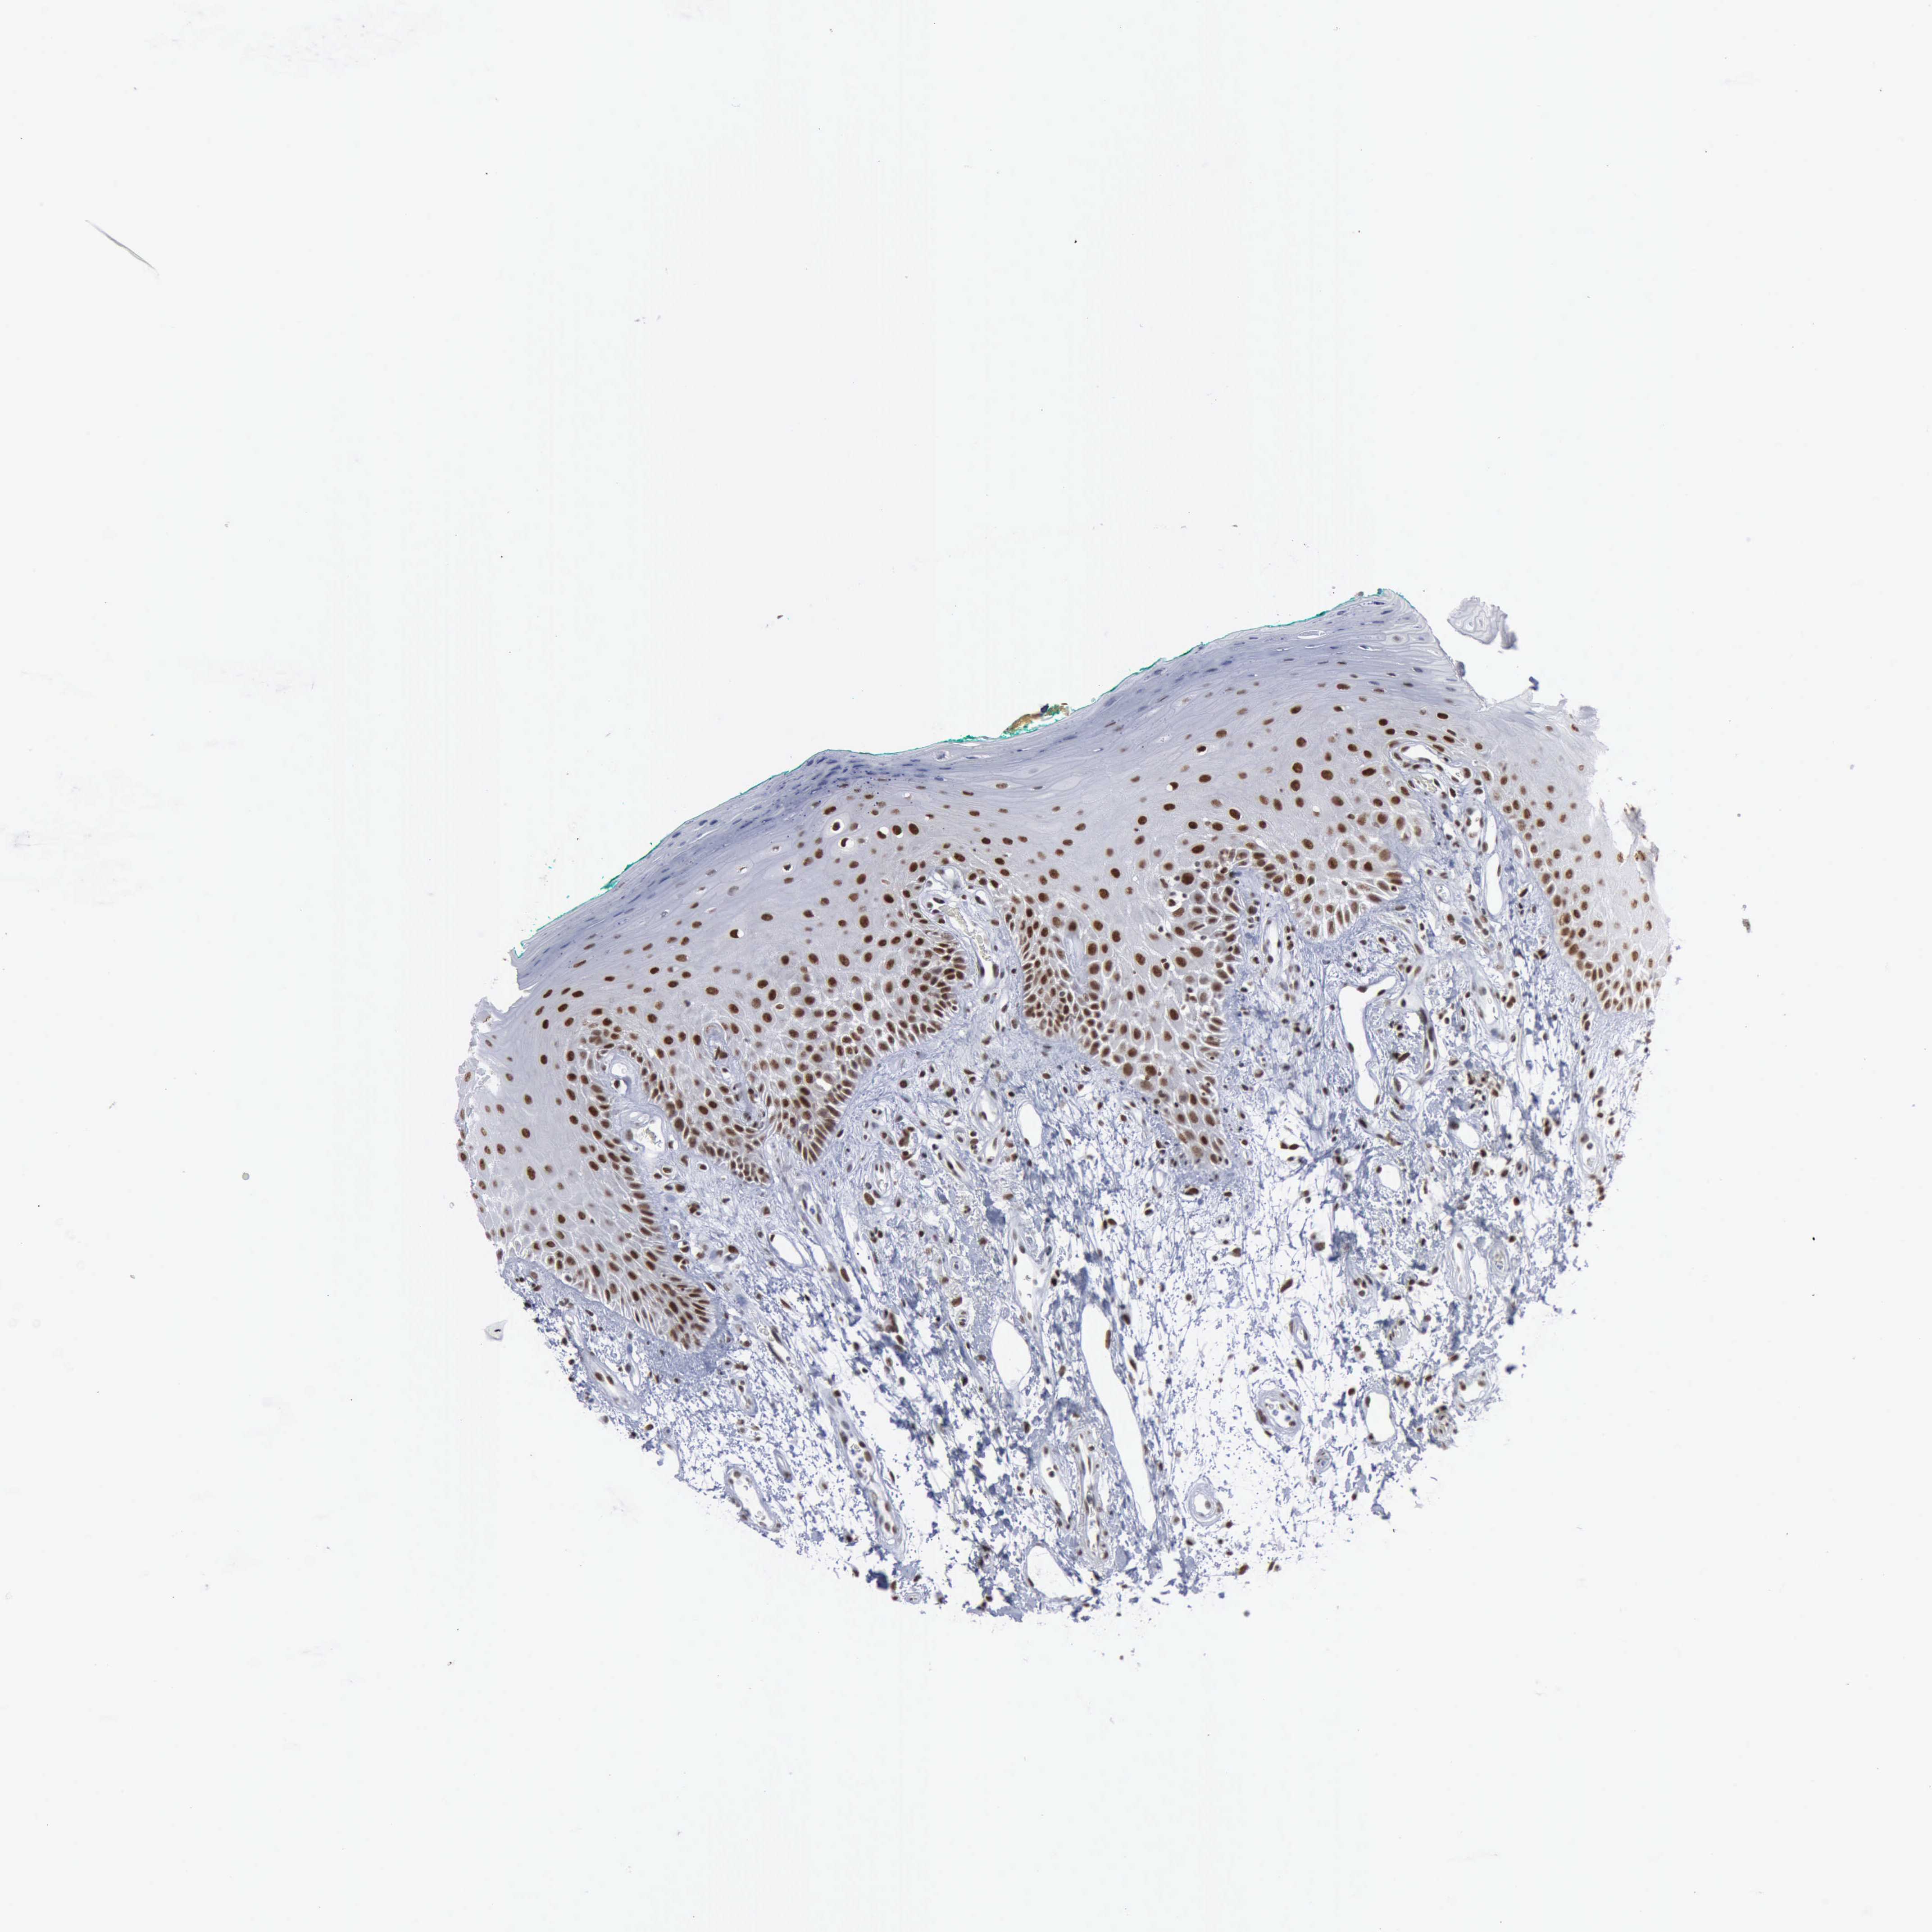

TISSUE PRIMARY DATA ORAL MUCOSA Show tissue menu

Oral mucosa

ORAL MUCOSA - Antibody stainingi

Antibody staining in the annotated cell types in the current human tissue is reported as not detected, low, medium, or high, based on conventional immunohistochemistry profiling in selected tissues. This score is based on the combination of the staining intensity and fraction of stained cells.

Each image is clickable and will lead to virtual microscopy that enables deeper exploration of all samples and also displays staining intensity scores, fraction scores and subcellular localization as well as patient and tissue information for each sample.

Antibody CAB000155

Squamous epithelial cells High